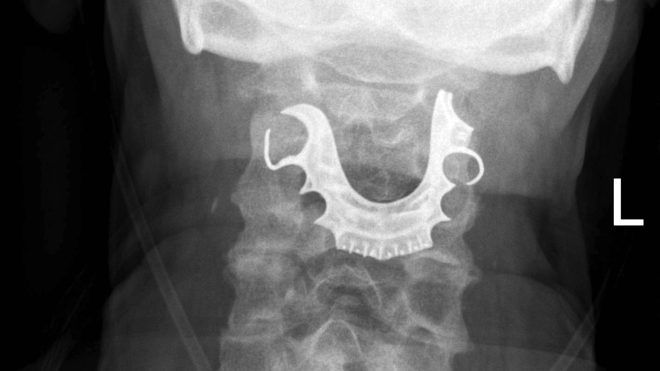

Karın bölgesinden rutin bir ameliyat geçiren erkek hasta, bu şikayetlerle birçok kez hastaneye gitti, yeni ameliyatlara girdi ve kan nakilleri yapıldı. Norfolk bölgesindeki James Paget Hastanesi, yaşananların ardından hasta bakım sürecinde değişiklikler yapıldığını açıkladı.

Hastanın başına gelenler, bilimsel yayın İngiliz Tıp Dergisi'nin Vaka Raporları bölümünde yayımlandı. Uzmanlar, hastanın ameliyattan önce genel anesteziyle uyutulmasından önce, takma dişlerin çıkartılmış olması gerektiğini vurguladı.